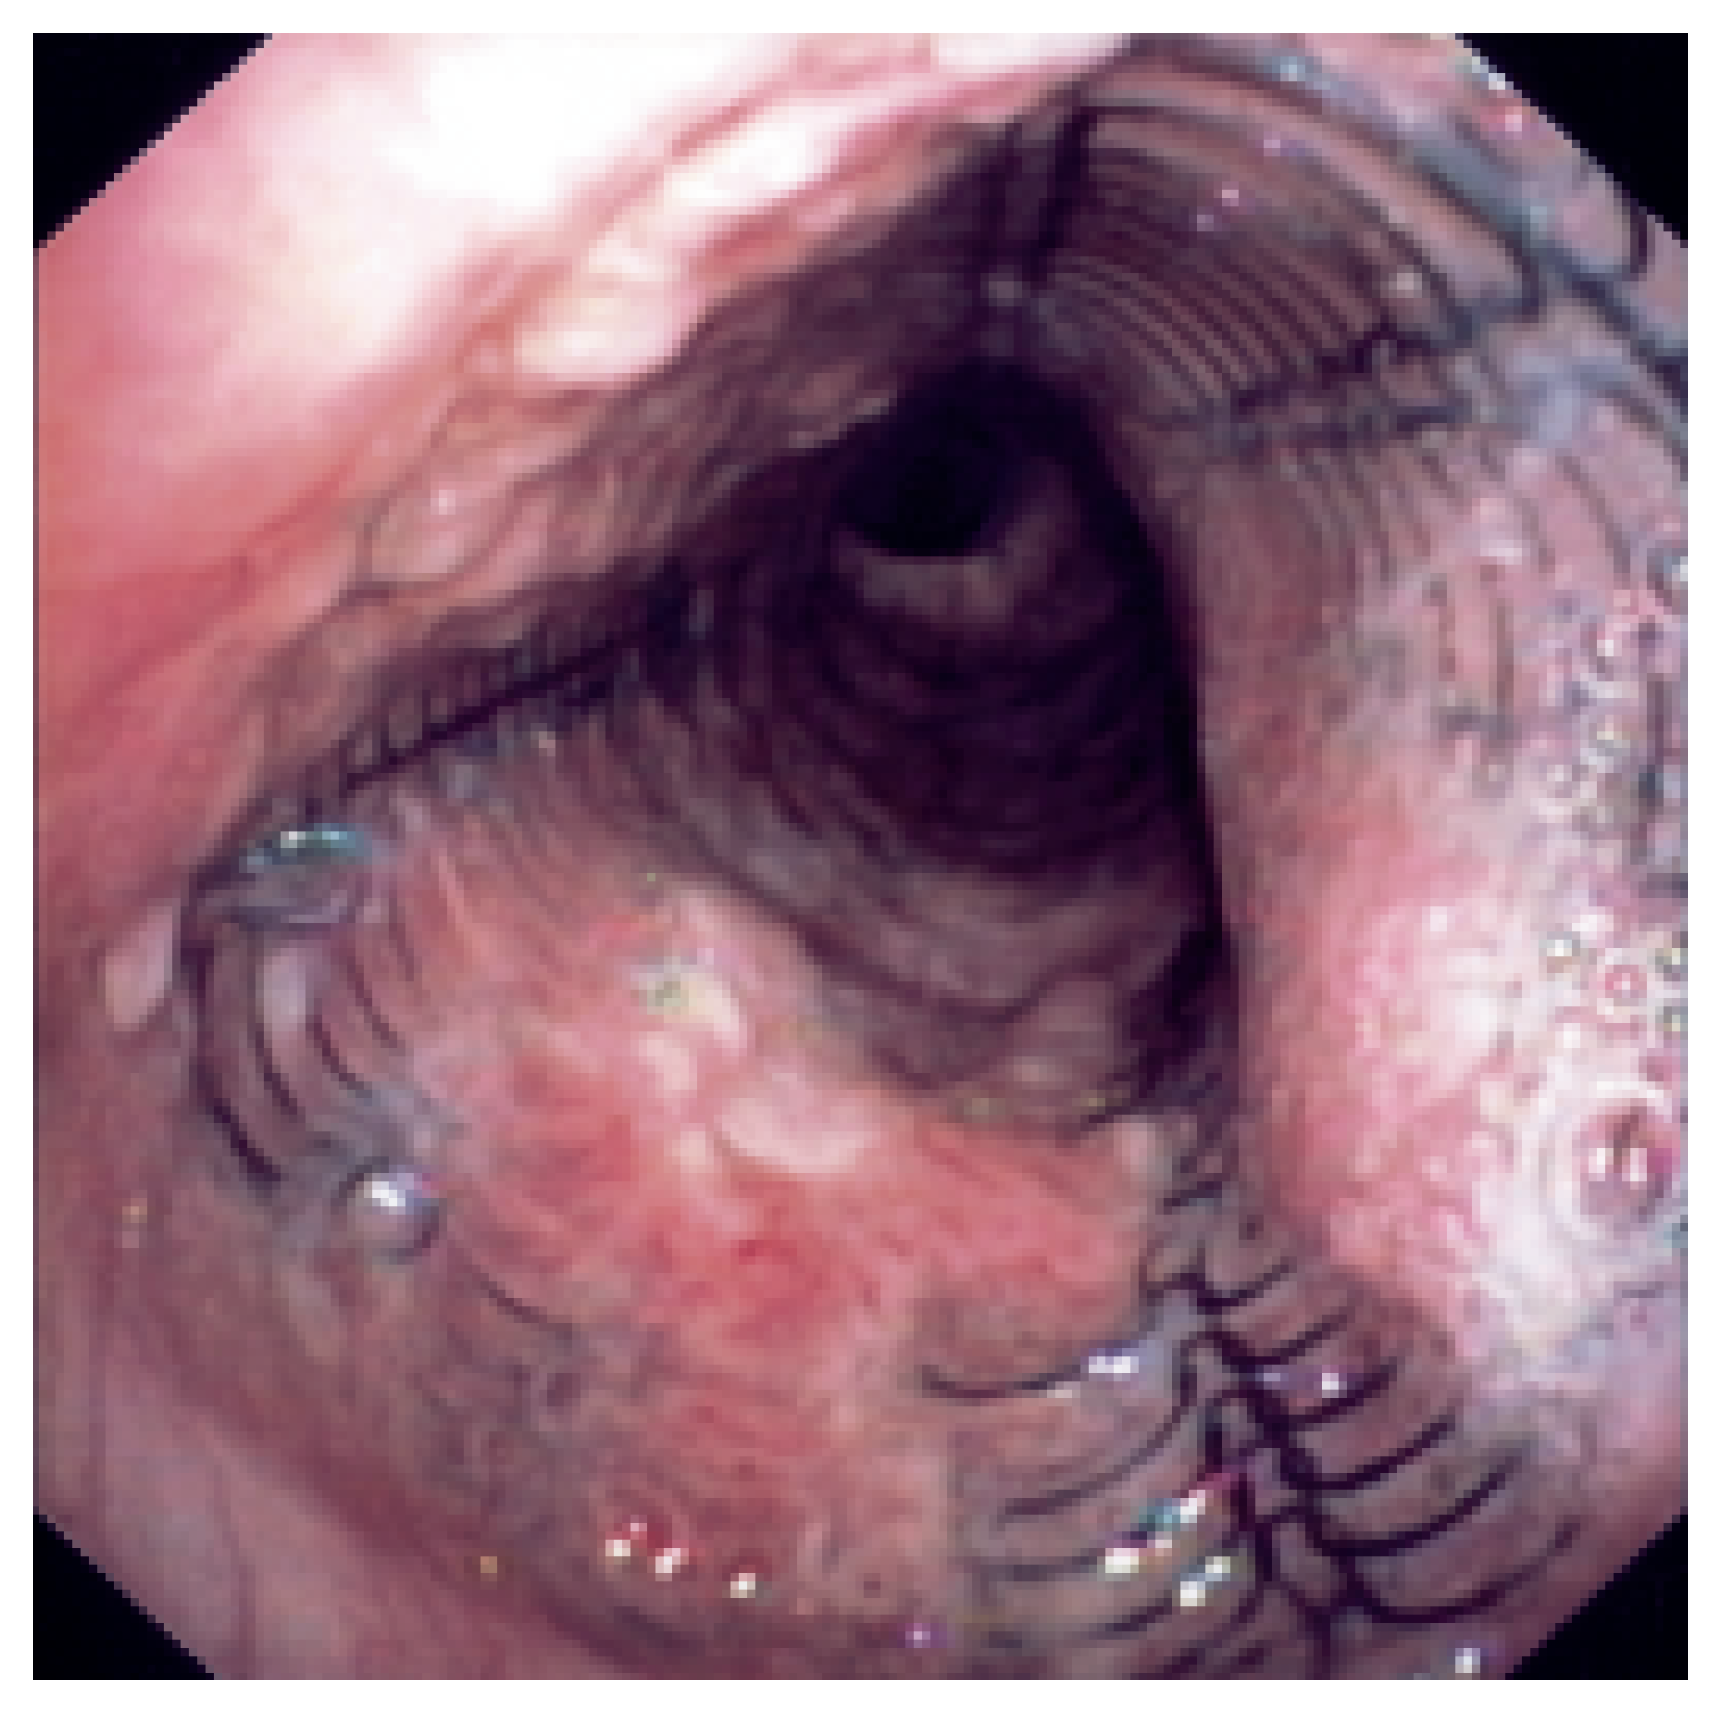

Abbildung 3. Dumon-Stent in der Trachea.